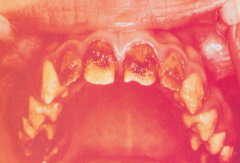

Meth mouth

-generalized extensive destruction of tooth surface -meth use

erosion

-loss of tooth structure w/ smooth polished surface -cause: chemical action, bulemia